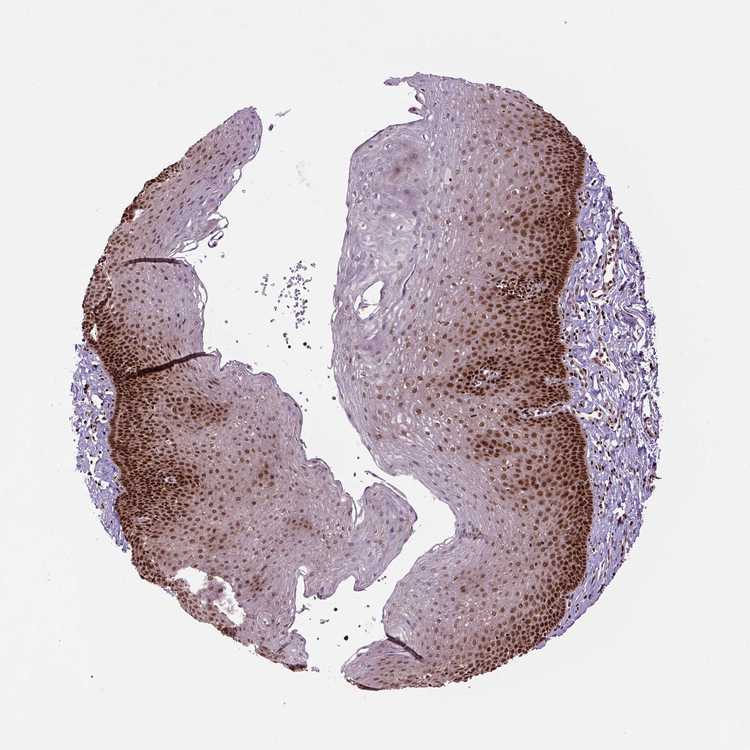

ESOPHAGUS - Antibody stainingi

Antibody staining in the annotated cell types in the current human tissue is reported as not detected, low, medium, or high, based on conventional immunohistochemistry profiling in selected tissues. This score is based on the combination of the staining intensity and fraction of stained cells.

Each image is clickable and will lead to virtual microscopy that enables deeper exploration of all samples and also displays staining intensity scores, fraction scores and subcellular localization as well as patient and tissue information for each sample.

Antibody CAB016114Antibody CAB069989

Squamous epithelial cells HighHigh